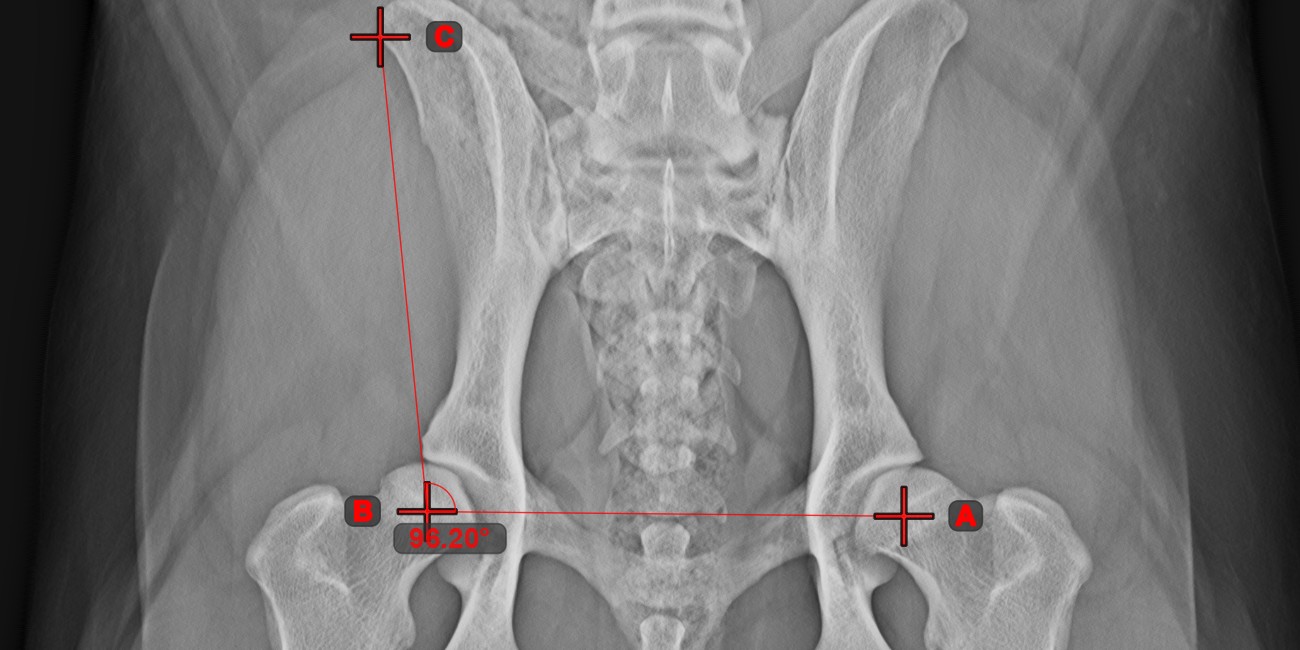

Winkel aus 3 Punkten¶

Das Werkzeug Winkel aus 3 Punkten

ist eine einfache und effektive Möglichkeit, einen Winkel anhand von nur drei Punkten zu berechnen.

Beginnen Sie, indem Sie das Werkzeug aus der linken Symbolleiste auswählen und einer der verfügbaren Maustasten zuweisen. Setzen Sie den Startpunkt der Anfangsseite, den Scheitelpunkt und den Endpunkt der Endseite des Winkels oder wählen Sie die Punkte aus der Szene aus. Die Seiten des Winkels werden automatisch konstruiert, wodurch der Winkel zwischen den Linien berechnet wird.

Ändern Sie die Position der drei Punkte, um den Bogen des Winkels mit dem Werkzeug Objekt auswählen/verschieben

zu ändern.